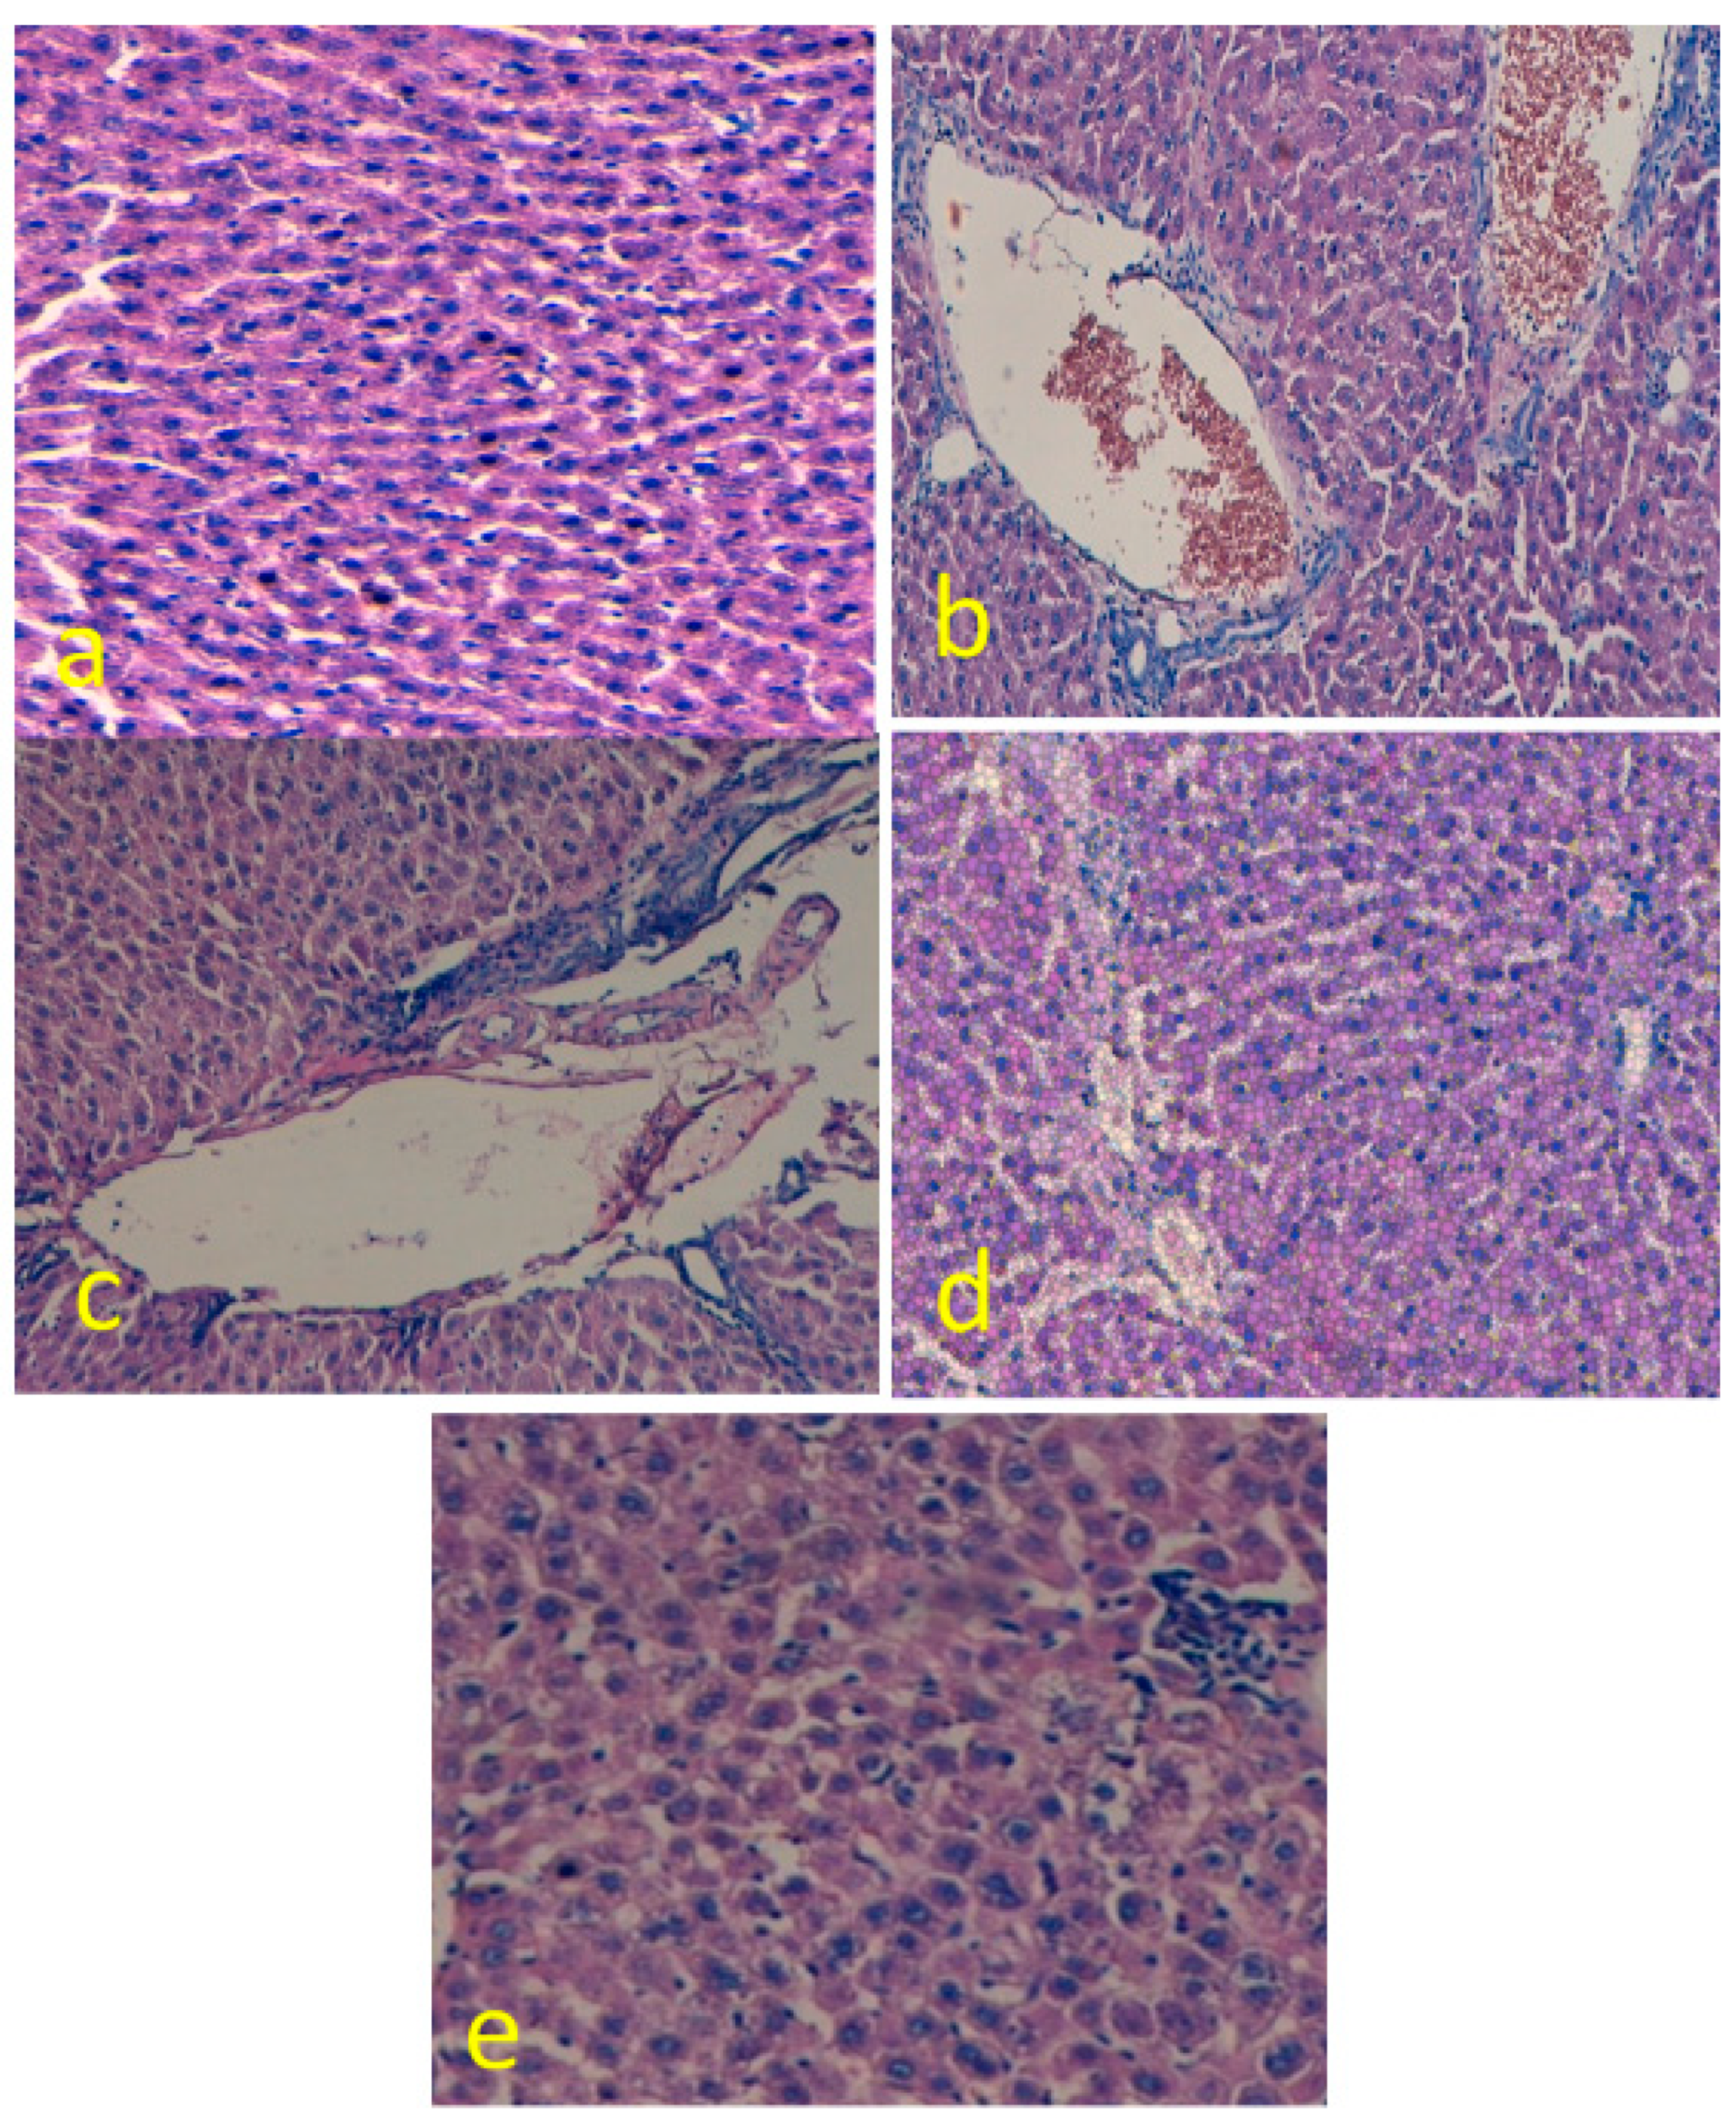

3.4. EGCG Reduces Hepatic Histological Alterations